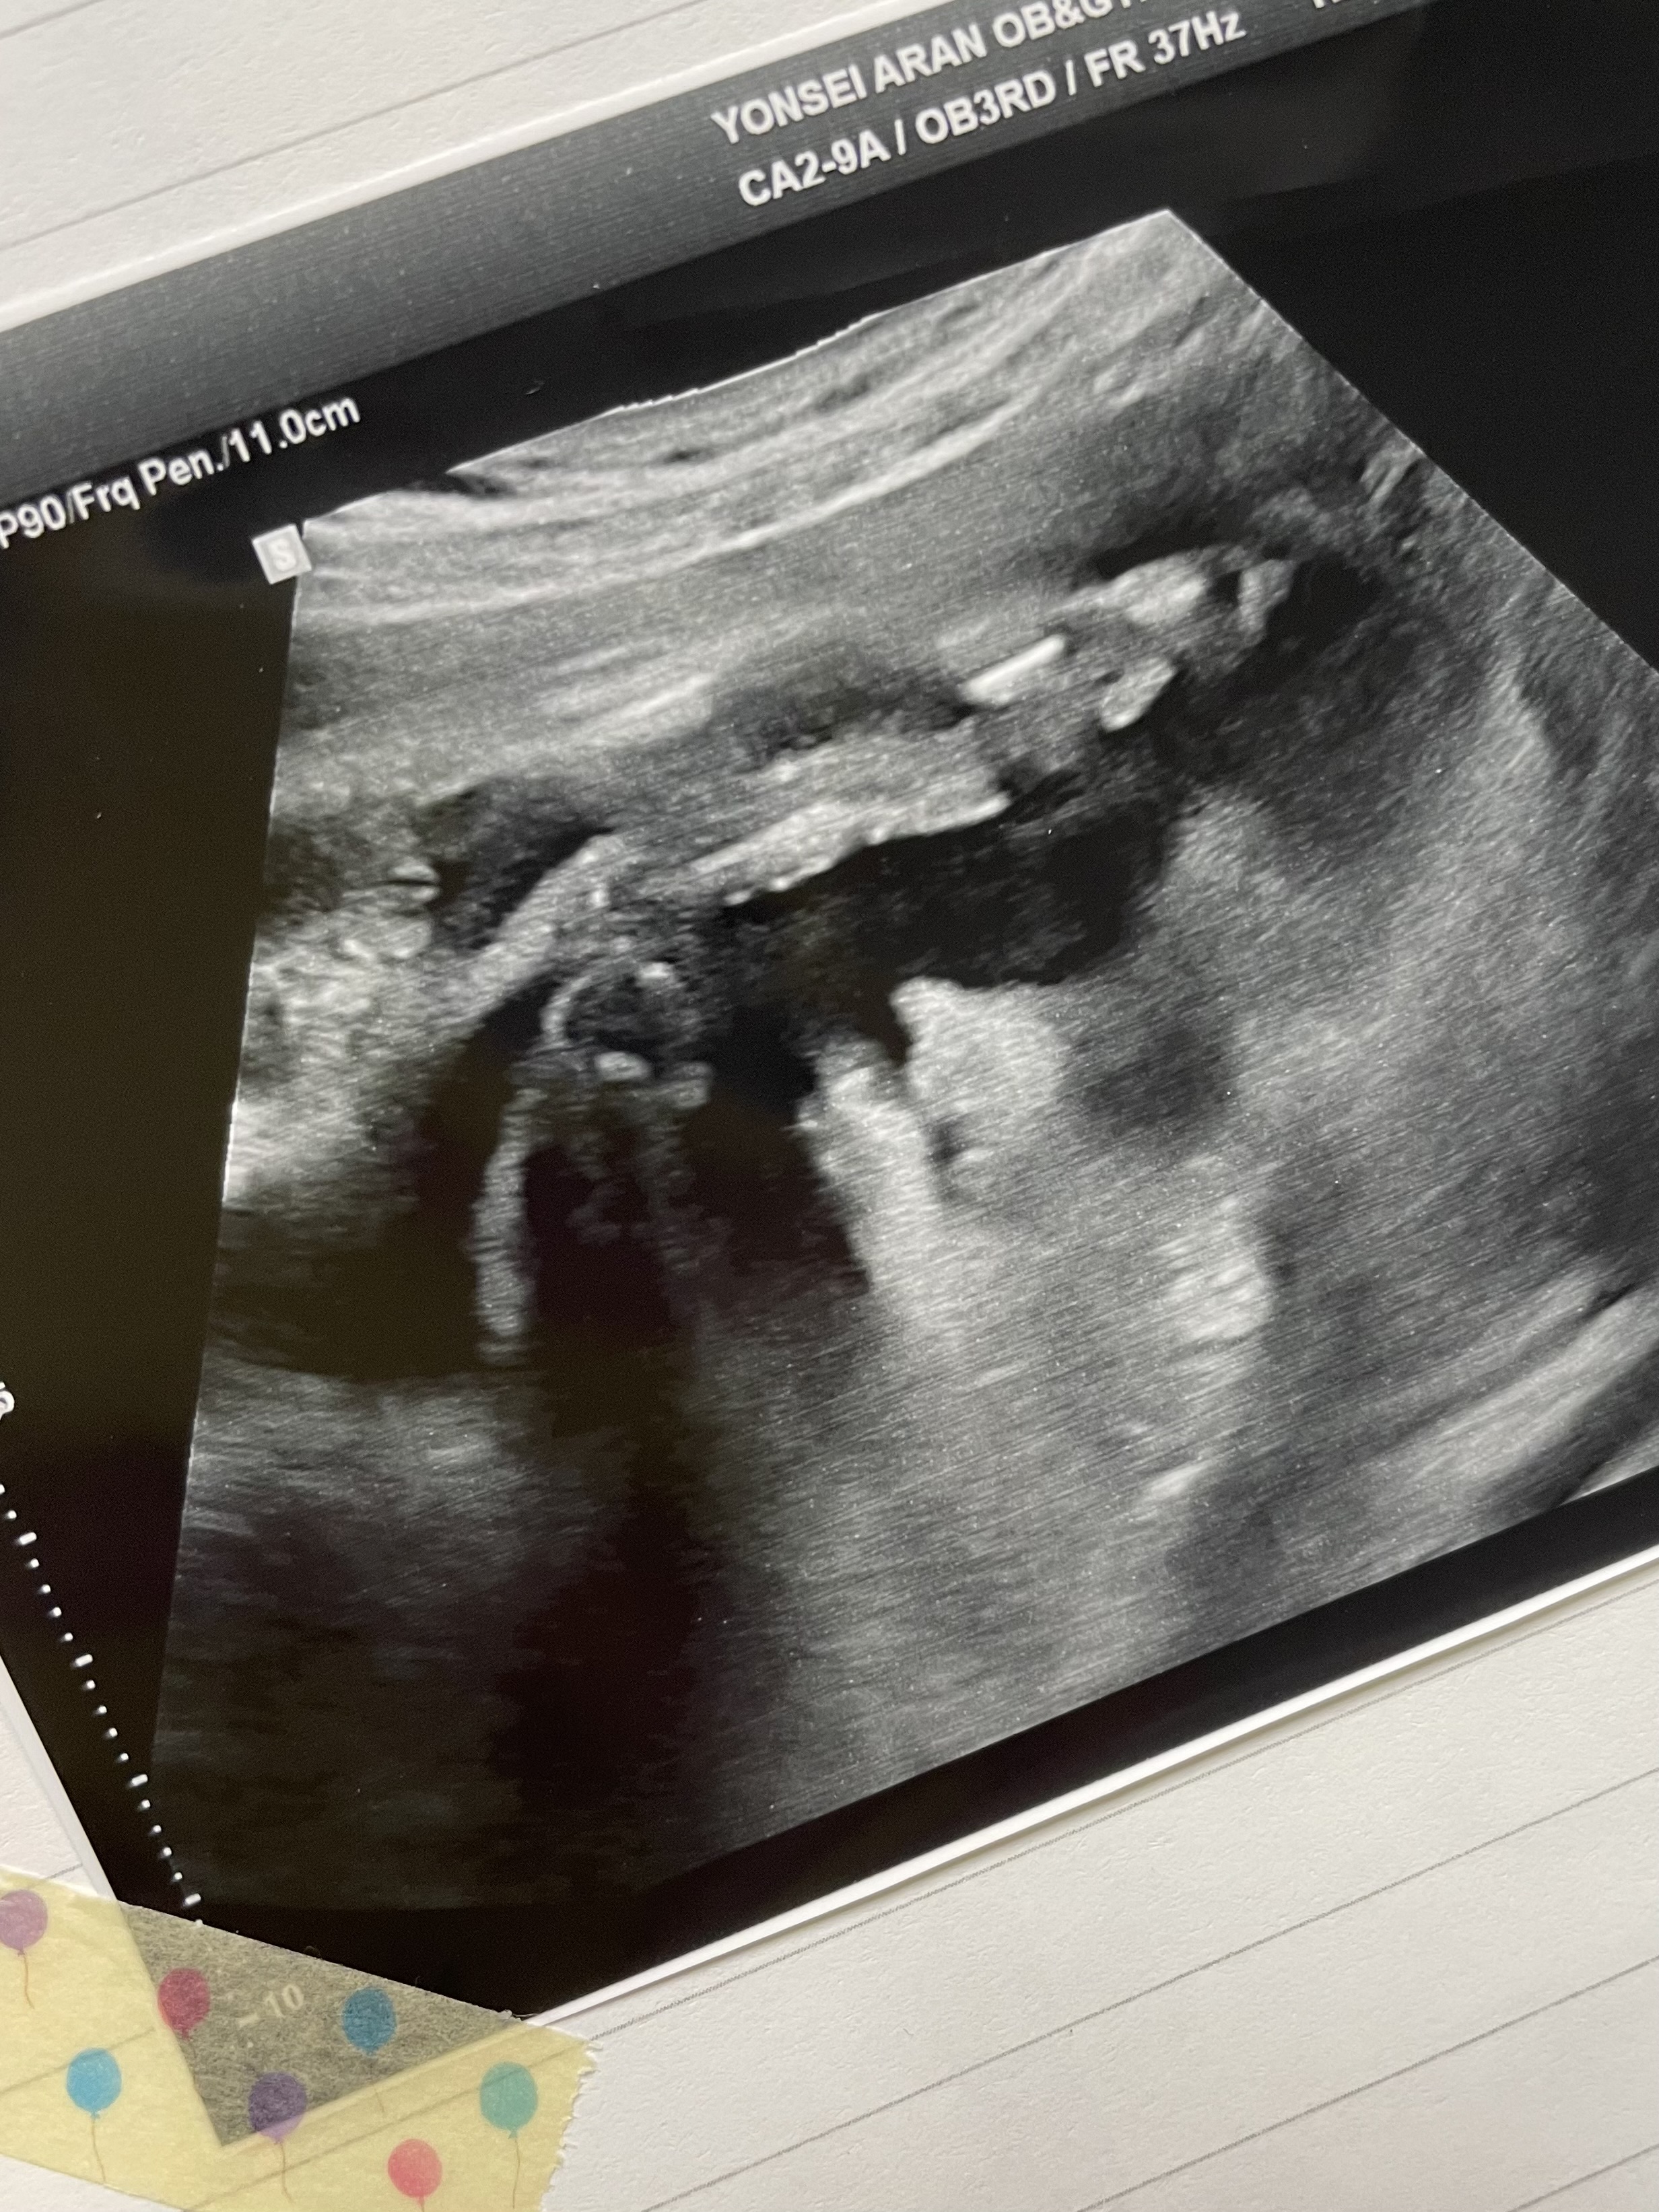

애기가 얼굴이 너무 잘보인다며 웃으셨다.

그와중에 머리는 역시 커졌고,